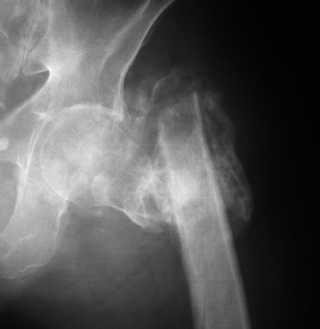

Если снимок справа по хронологии последний, то в тазобедренном сустава наступил анкилоз. Это хороший плюс костной ткани для постановки чашки эндопротеза, но отсутствие сохранения биомеханической оси бедренной кости ставит под вопрос благоприятный вариант усановки ножки эндопротеза.... Учитывая выполненную остеотомию, не считаю выполнение скелетного вытяжения лишенным смысла, для восстановления оси конечности с последующим, возможно, индивидуальным эндопротезированием.

Очень признателен Вам за ответ, но позвольте мне не согласиться с Вами. Я бы пока не делал вывод о анкилозировании тазобедренного сустава. На рентгеновских снимках, да и по данным компьютерной томографии (а этот метод один из самых современных и информативных), хорошо прослеживается постоянной ширины щель между головкой бедренной кости и вертлужной впадины. Кроме того, несложно увидеть разницу "шеечно-диафизарного угла" до и после выполнения тракции в аппарате. Хотя, Алексей, даже если я и прав, это не сильно облегчает нашу задачу.

Случай крайне нестандартный. Поэтому путей решения - правильных - может быть несколько . Или ни одного... Гвоздь - со своим пациентом - нет, я бы не рискнул. Боюсь, не получится, хотя и опыт определённый есть, в своё время, уже более 10 лет назад, мы были в числе тех, кто начинал БИОС в России... Но - не тот случай, мне кажется. Эндопртез, согласен - куда перспективнее, если от Ргр отталкиваться, а не от пациента. Ведь он и на вытяжение, и на дистракцию в аппарате отреагировал нагноением. Очень опасно, сейчас, во всяком случае. АВФ? Наверное, один из немногих случаев, когда это лучшее из решений, мне кажется. Андрей Волна

2 вариант. Только сразу произвести и резекцию проксимального отдела бедренной кости под ревизионный эндопротез. На счет 1 варианта - получите укорочение, нет гарантии что анибактериальное покрытие поможет, операция получится не менее травматичная (все равно нужно открыть широко для полноценной ревизии и резекции некротизированной кости). По 2 варианту - полноценная ревизия с удалением даже сомнительных участиков кости на фоне хорошей избирательной антибиотикотерапии и улучшения капиллярного кровоснабжения, не будет укорочения, если боитесь что не удержится - зафиксируйте минимальным стержневым аппаратом.

Остеосинтез: не очень хорошо виден весь прокисмальный отломок - чем больше пенек ниже большого и малого вертелов - тем более эффективней будет интрамедуллярный остеосинтез например Y-Nail, но угол надо подобрать больше 135 гр для коррекции длины, больше угол - длиньше нога, примерно 10 гр = 1 см. Если проксимальный отломок заканчивается сразу за малым вертелом или латеральнее выше, то следует примерить пластину типа LISS or LSPDF, но лучше та, где отверстия не совмещенные, а одинарные. На операции дистальный отломок отводите под нужным углом 150 гр, к примеру, вводлите 5 винтов в проксимальный отдел = вертела и шейка, затем с торцевой компрессией фиксируете 8-и т.д. винтами диафиз к пластине. После приведения ноги - длина должна быть одинакова, сустав по-моему вполне жизнеспособен. Теперь остается тлько защититься от вторичного нагноения: был ранее в Росии Touralin - сильно помогал, ну а теперь - антибиотики - местно и в огранизм, стабильный остеосинтез, достатоточная гемоперфузия отломков. Пластического материала для осётеогенеза мне кажется там хватит, его можно измельчить и смешеть с анибиотиками - депо и того и другого. и Как говаривал Н.И. Пирогов:"операцию мы сделали, а теперь Бог вылечит!".